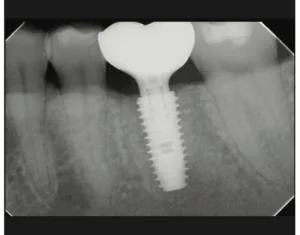

INTRODUCTION Osseointegration, as defined by Brånemark, is a direct structural and functional connection between ordered, living bone and the surface of a load-carrying implant.1 The